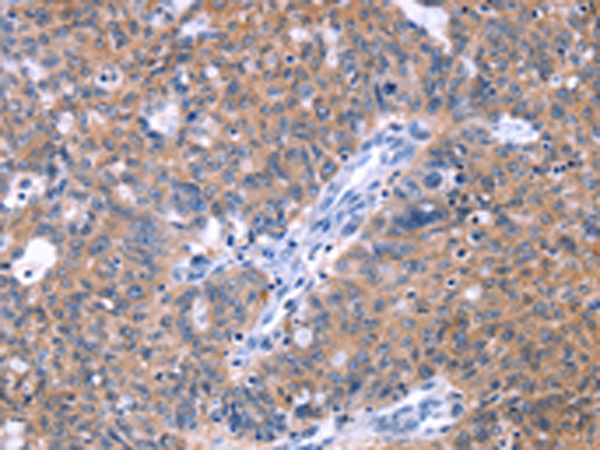

分类: 科研抗体货号: P04992别名: KV6.3; KV10.1应用: WB,IHC反应种属: Human, Mouse, Rat